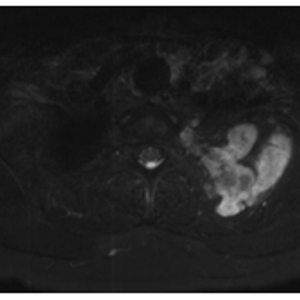

在骨肿瘤科专家门诊,刘巍峰主任医师接诊了陈女士。在仔细询问病史、查体以及完善了相关检查后,诊断为左侧第二肋骨软骨肉瘤累及第一和第三肋,并向胸椎侧、胸腔内和胸腔外颈椎旁侵犯,需手术切除,并且需要开胸手术+锁骨下血管探查+锁骨下臂丛神经探查。而软骨肉瘤是一类间叶来源恶性骨肿瘤,治疗方法主要依靠手术,且安全的外科边界尤为重要。

病变部位MRI

考虑到陈女士的病情在近2个月内进展明显,症状持续加重,孙扬主管医师尽快为病人安排住院。全科查房中,牛晓辉、张清、郝林、鱼锋等资深专家提出治疗建议,治疗组讨论并制定了第1-3肋骨肿瘤整块切除,锁骨下血管+臂丛神经探查,开胸肺脏探查备受累肺叶楔形切除的手术方案。因肿瘤后方为肩胛骨,上方为锁骨及胸廓出口,肿瘤向前凸入胸腔可能与肺存在粘连,病变区视野暴露即存在一定困难,且一旦血管损伤大出血及臂丛损伤导致的上肢功能障碍,都将带来严重后果。此外,切除第1-3肋后,为避免发生胸廓软组织塌陷,还需进行胸壁重建。基于此,针对手术难度大、风险高、需要多学科协作进行。

病变位于第2后肋,其后方为肩胛骨,并与锁骨下血管、臂丛神经解剖毗邻